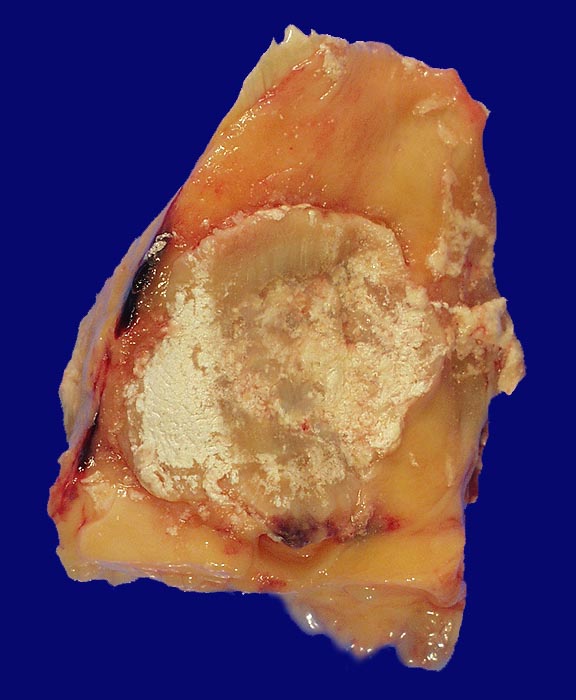

Arthritis urica

Weisse Ablagerungen (Uratkristalle) auf der Hinterseite der Patella bei Arthritis urica